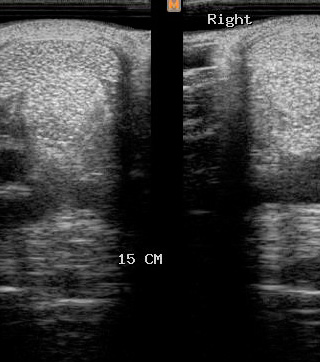

Ecografía

Cuenta con Ecografía digital de alta complejidad.

17 años de experiencia siendo una de las ecografistas más reconocidas en la práctica de equinos. Realiza pasantías en la universidad de Davis California y en Mid-Atlantic Equine Medical Center en New Jersey.